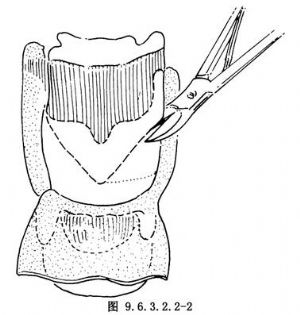

10.5 5.切開甲狀軟骨

從患側甲狀軟骨上角起向中線至甲狀軟骨上2/3和1/3交界水平延至對側(圖9.6.3.2.2-2)。用圓鋸或骨剪沿此標誌線切開軟骨,患側軟骨瓣備用,其餘部分取除。